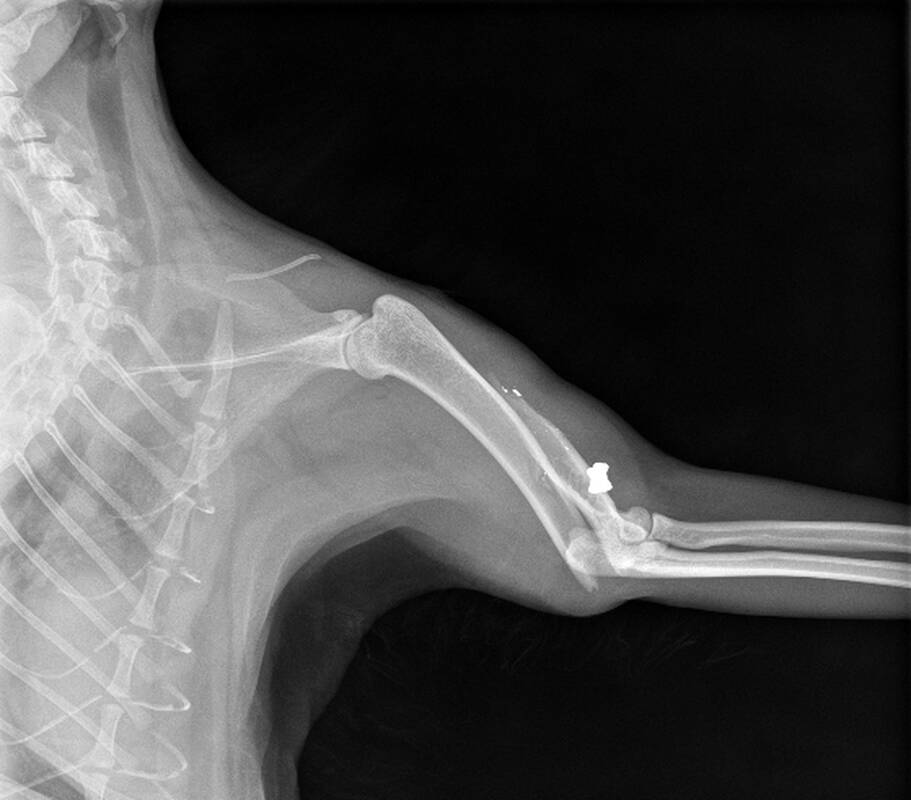

„Nuvežėme į veterinarijos kliniką. Atliktas rentgeno tyrimas parodė, kad kairiajame petikaulyje yra įstrižinis lūžis, galimai sukeltas pneumatinio ginklo šovinio. Nuotraukoje matyti ir skeveldros su šovinio pėdsakais. Mokšą buvo galima operuoti, tačiau po operacijos jai būtų tekę būti narve apie tris keturis mėnesius be galimybės vaikščioti, nes vienos kojos katė jau neturėjo, o pašautoji buvo atraminė. Kad nejudėtų, būtume turėję jai girdyti kažkokių vaistų, nes Mokša buvo labai judri. Tokios sąlygos būtų tarsi jos kankinimas. Kad katė nesikankintų, nusprendėme ją užmigdyti“, – jautriai apie augintinės netektį atviravo kaunietis.